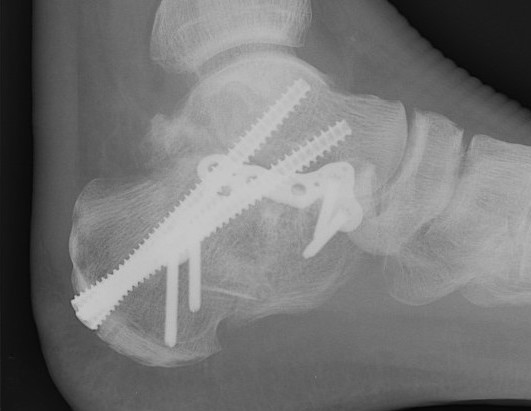

Intramedullary nail

C-Nail

Medin you-tube C-nail animated surgical technique

Vumedi C-nail surgical technique

Reduction

- tuberosity Schantz pin

- percutaneous reduction / K wire fixation or

- sinus tarsi approach to reduce and screw fixate posterior facet

Insertion

- below achilles tendon

- aim towards ST joint